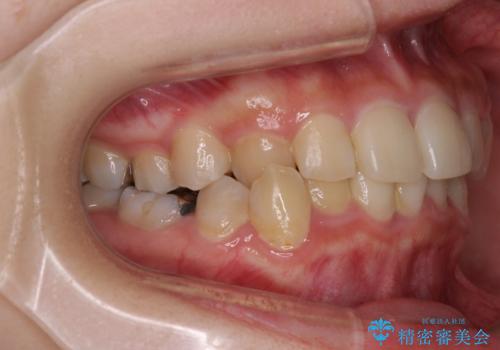

- 犬歯のクロスバイトを気にして来院された患者様です。

マウスピース矯正とワイヤー矯正の両方を提案しましたが、インビザラインの自己管理が煩わしいとのことで、ワイヤー装置による矯正治療を行うこととしました。

犬歯は歯根が太くて長いため、クロスバイトを改善するのは大変であることが多いですが、比較的スムーズに改善することができました。

インビザラインであったら、もっと期間はかかっていたような印象です。